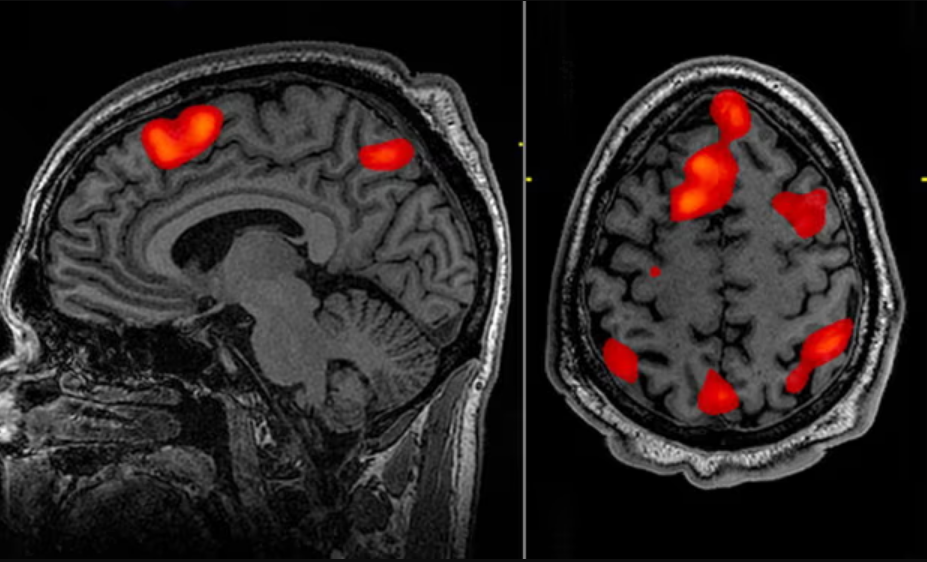

뇌과학 인공지능은 뇌의 구조와 기능을 이해하고, 이를 통해 인간의 행동과 사고를 밝혀내는 학문입니다. 뇌과학 인공지능은 뇌와 인공지능의 융합 연구로, 뇌의 정보처리 방식과 인지기능을 연구하고, 이를 모방하거나 개선하는 인공지능 시스템을 개발합니다.

- 의료: 뇌 손상이나 질병을 진단하고 치료하는 데 사용됩니다. 예를 들면, 뇌졸중, 파킨슨병, 알츠하이머병, 우울증, 자폐증 등의 뇌 관련 질병을 뇌영상 기술과 인공지능을 통해 정확하게 판단하고, 뇌컴퓨터 인터페이스나 뇌자극 기술을 통해 뇌 기능을 회복하거나 개선할 수 있습니다.